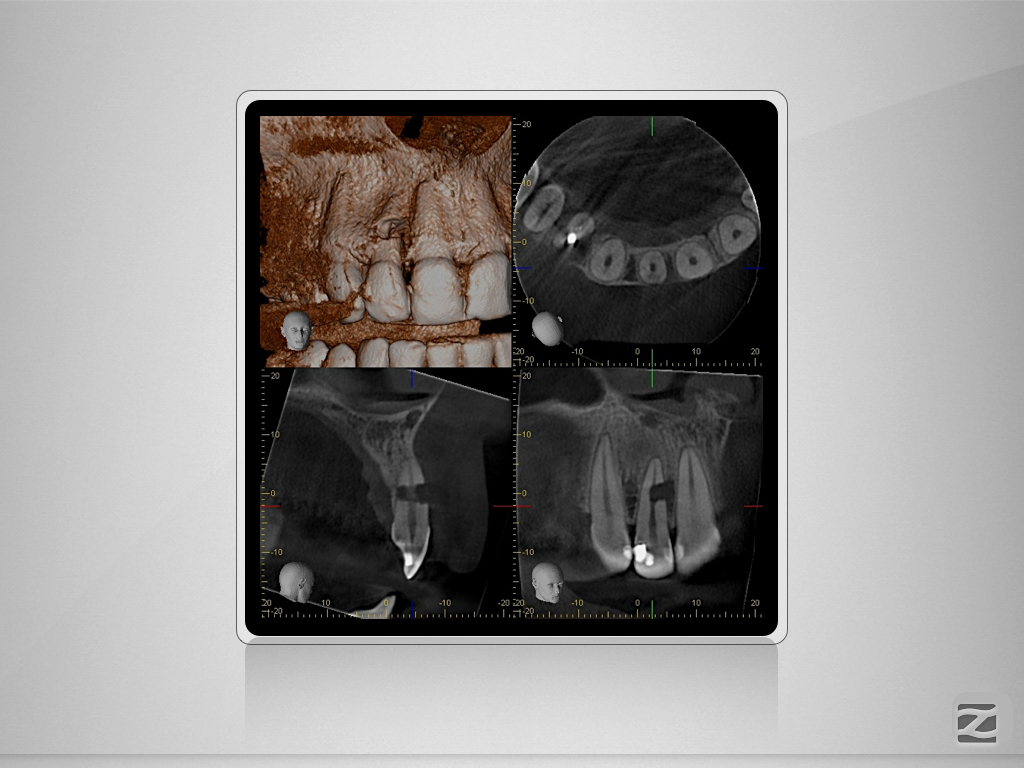

Perforierende interne Resorption